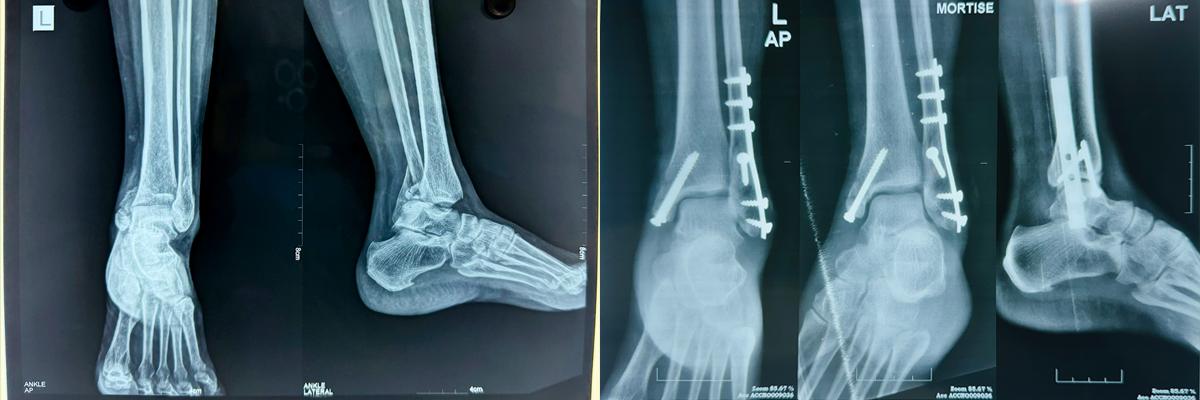

ORIF Ankle fixation1

12. Types of Surgical Fixation Techniques

Surgical options include:

• K-Wire fixation

• Bone plating

• Interlocking nails

• Cabling techniques

Each technique is chosen based on the fracture’s location, complexity, and Patient health.